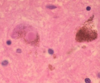

Progressive Multifocal Leukoencephalopathy

Opportunistic JC virus

Invasion and destruction of oligodendrocytes

JC virus inclusions in oligodendrocytes